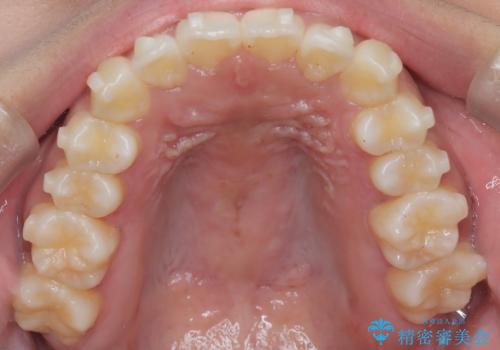

【インビザライン】笑ったときに目立つ八重歯をなおしたい

- 笑ったときに八重歯が見えることを主訴に来院されました。

下の前歯が一本足りない患者様でしたので、シミュレーションを作り、事前に患者様と治療ゴールのイメージをしっかり共有したうえでインビザラインを用いて治療を行っています。

奥歯を後ろのほうに動かすことで、前歯も少し下がることができ、矯正後の口元も満足していただきました。

下顎の前歯が一本ない場合は上下の正中は合いません。